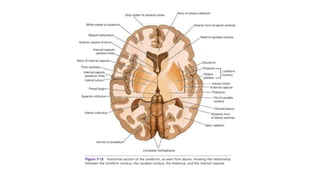

1. ACA : medial aspect of the cerebral

• Medial lenticulostriate arteries :globus

the putamen

• Recurrent artery of Heubner : IC,

2. MCA : majority of the lateral surface of the

• Lateral lenticulostriate arteries: Lateral

capsule as well as the upper internal

3. Anterior Choroidal artery : branch of ICA and

thalamus,optic tract ,GP, CN etc

4. PCA : posteromedial surface of the temporal

lobe and the occipital lobe